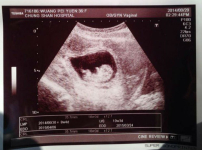

劉畊宏王婉霏懷第三胎 稱上帝所賜超乎所求

《壹週刊》拍到台灣藝人劉畊宏與太太王婉霏上婦產科求診的照片。昨天他在微博大方承認太太懷了第三胎,將為他們家帶來更大的喜悅。信奉基督教的他說:「上帝給的超過所想所求」。